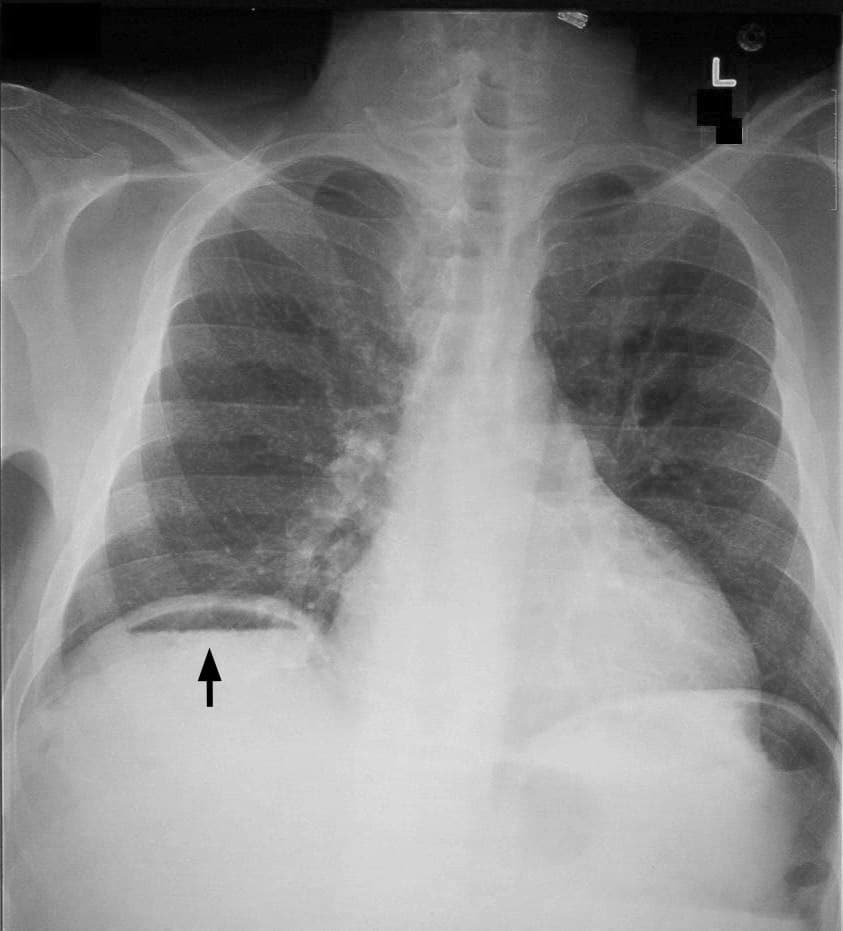

Pneumoperitoneum is pneumatosis (abnormal presence of air or other gas) in the peritoneal cavity, a potential space within the abdominal cavity. The most common cause is a perforated abdominal organ, generally from a perforated peptic ulcer, although any part of the bowel may perforate from a benign ulcer, tumor or abdominal trauma. A perforated appendix seldom causes a pneumoperitoneum. Spontaneous pneumoperitoneum is a rare case that is not caused by an abdominal organ rupture. This is also called an idiopathic spontaneous pneumoperitoneum when the cause is not known. In the mid-twentieth century, an "artificial" pneumoperitoneum was sometimes intentionally administered as a treatment for a hiatal hernia. This was achieved by insufflating the abdomen with carbon dioxide. The practice is currently used by surgical teams in order to aid in performing laparoscopic surgery. Perforated duodenal ulcer – The most common cause of rupture in the abdomen. Especially of the anterior aspect of the first part of the duodenum. Perforated peptic ulcer Bowel obstruction Ruptured diverticulum Penetrating trauma Ruptured inflammatory bowel disease (e.g., megacolon) Necrotising enterocolitis/pneumatosis coli Bowel cancer Ischemic bowel Steroids After laparotomy After laparoscopy Breakdown of a surgical anastomosis Bowel injury after endoscopy Peritoneal dialysis (PD), although the prevalence of pneumoperitoneum is estimated to be less than 4% among people with PD in a more recent study in the United Kingdom. Vaginal insufflation (air enters via the fallopian tubes; e.g., water-skiing, oral sex) Colonic or peritoneal infection From chest (e.g., bronchopleural fistula) Non-invasive PAP (positive airway pressure) can force air down duodenum as well as down trachea. A spontaneous pneumoperitoneum is a rare case that is not caused by an abdominal organ rupture. This is also called an idiopathic spontaneous pneumoperitoneum when the cause is not known.